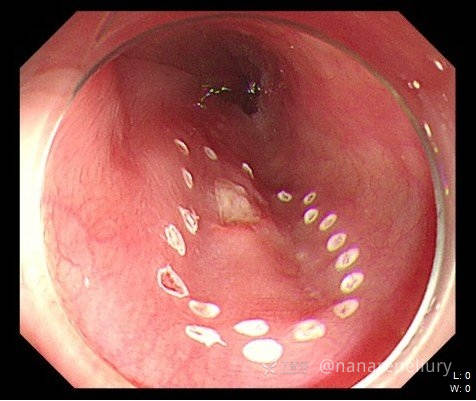

一例食管早癌病例分享

临床诊断:食管早癌

治疗经过:后行ESD治疗,ESD术后病理:

(食管黏膜ESD标本)鳞状细胞癌,中分化;小灶浸润至固有层;侧切缘及基底切缘阴性。

ESD图片: